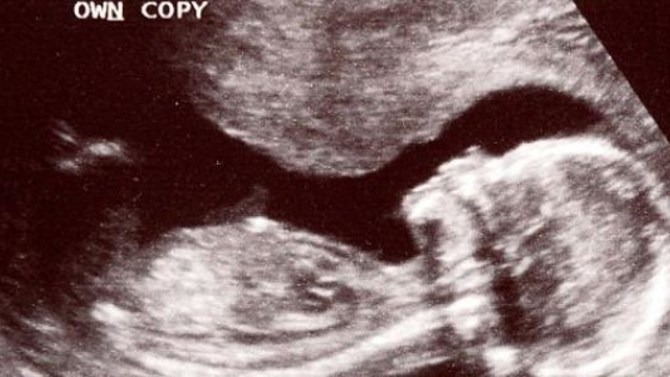

Назарларыңызға ұсынылып отырған оқиға қиялдан туған дүние болып көрінуі мүмкін, алайда бұл шындық. Дәрігер әйелге іште өлген баланы алдырту үшін жасанды түсікке арналған дәрілер жазып береді. Бірнеше күннен кейін УДЗ көрсеткіші іштегі баланың тірі екенін көрсетеді.

УДЗ тексеруі кезінде дәрігер үнсіз шығып кетіп, артынша өзінің әріптесімен оралған. Келген дәрігердің айтуы бойынша сәбидің жүрегі соғып тұрған. Дәрігер ұсынған дәрілер әйел мен баланың өміріне қауіп төндірген.